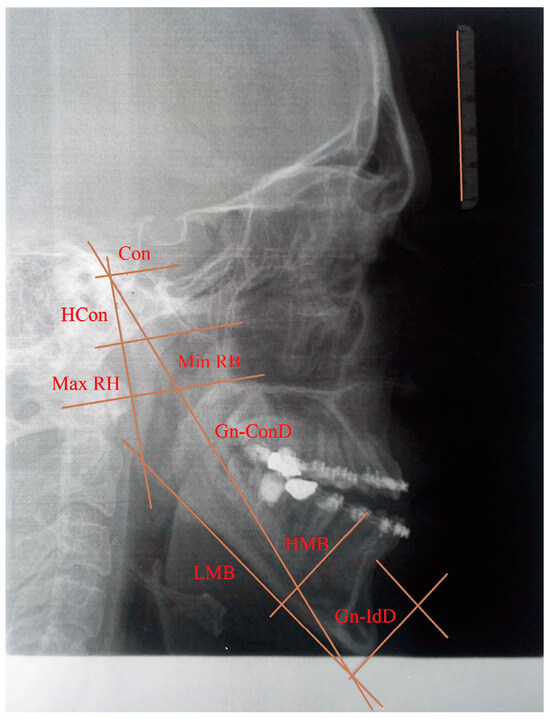

• Gnathion-interdental distance (Gn-IdD)—distance from the Gnathion to the alveolar septum between two incisors;

• Bigonial width (Go-GoD)—direct distance between right and left Gonion;

• Length of the mandibular body (LMB)—distance between Gonion and Gnathion;

• Gnathion-condylar distance (Gn-ConD)—distance between the Gnation and condylion (most prominent point on the mandibular condyle) anatomical points;

• Height of the mandibular body (HMB)—distance from the alveolar border to the mandibular base at the level of the Mental Foramen;

• Minimum ramus breadth (Min RB)—minimum breadth of the mandibular ramus measured perpendicular to the plane of the maximal height of the ramus;

• Maximum ramus height (Max RH)—distance between the highest point on the mandibular condyle and Gonion;

• Height of the condyle (Hcon)—distance between the condylion and the axis of the most inferior point of mandibular notch perpendicular to Max RH.

The input data for this analysis consisted of the measured values of morphometric parameters obtained from the 2D X-ray image and the 3D model of the patient. Due to the lack of both condylar processes, eight morphometric parameters (bigonial width, maximum ramus height, height of the condyle, length of the mandibular body, minimum ramus breadth, Gnathion–condylar distance, height of the mandibular body, and Gnathion–interdental distance) are used and presented in Figure 1. The measured morphometric parameters from the 2D image (length of the mandibular body, height of the mandibular body, height of the condyle, minimum ramus breadth, maximum ramus height, Gnathion–condylar distance, and Gnathion–interdental distance) were scaled according to the etalon size. The morphometric parameter bigonial width was measured from a 3D model of the patient using CATIA V5 R21, 3D CAD software. The measurements of the eight morphometric parameters are presented in Table 3. As a consequence of the excessive development of the mandible in the anterior direction, abnormal anatomical structures occur within the occlusion and the values of the morphometric parameters regarding the length of the mandibular body and Gnathion–condylar distance are high.

Figure 1. Morphometric parameters positioned on the X-ray image.